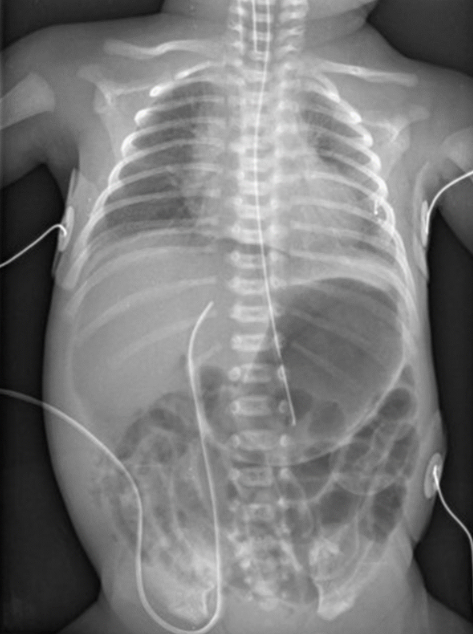

임신 31주, 출생체중 920 g의 여아가 출생 6일 째이다. 환아는 2일 전부터 무호흡, 발열, 복부 팽만, 혈변이 나타났다. 현재 경관 영양 공급을 하고 있다. 혈액검사와 복부 X선 검사 결과는 다음과 같다. 가장 적절한 조치는 무엇인가?

Imp: pneumoperitoneum, Neonatal necrotizing enterocolitis

재태연령 31주, 출생 체중 920g의 출생 6일 신생아가 복부 팽만, 무호흡, 발열, 혈변 등의 증상이 있다. 조산아에서 장관영양을 하다 발생한 복부 팽만, 구토, 혈변 등의 증상을 통해 신생아 괴사성장염을 의심할 수 있다. 또한 AXR에서 창자벽공기증, 기복증(복강의 outline이 air로 윤곽이 드러남)이 관찰되고 있기에 괴사성장염으로 인한 장 천공이 기복증까지 일으켰다고 볼 수 있다.

• 신생아괴사성장염의 치료는 금식 및 코위관 삽입, 수분 공급 등의 보존적 치료이지만, 장천공이 발견된 경우에는 응급개복술을 해야한다.